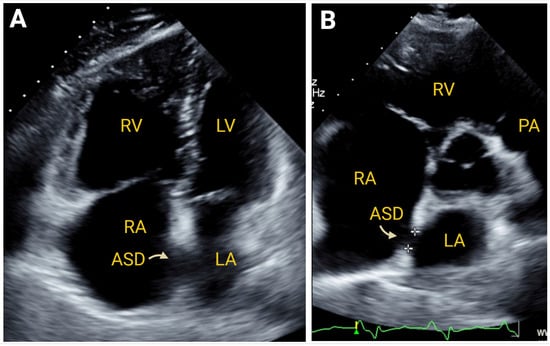

7.2.3. Simple Congenital Heart Defects